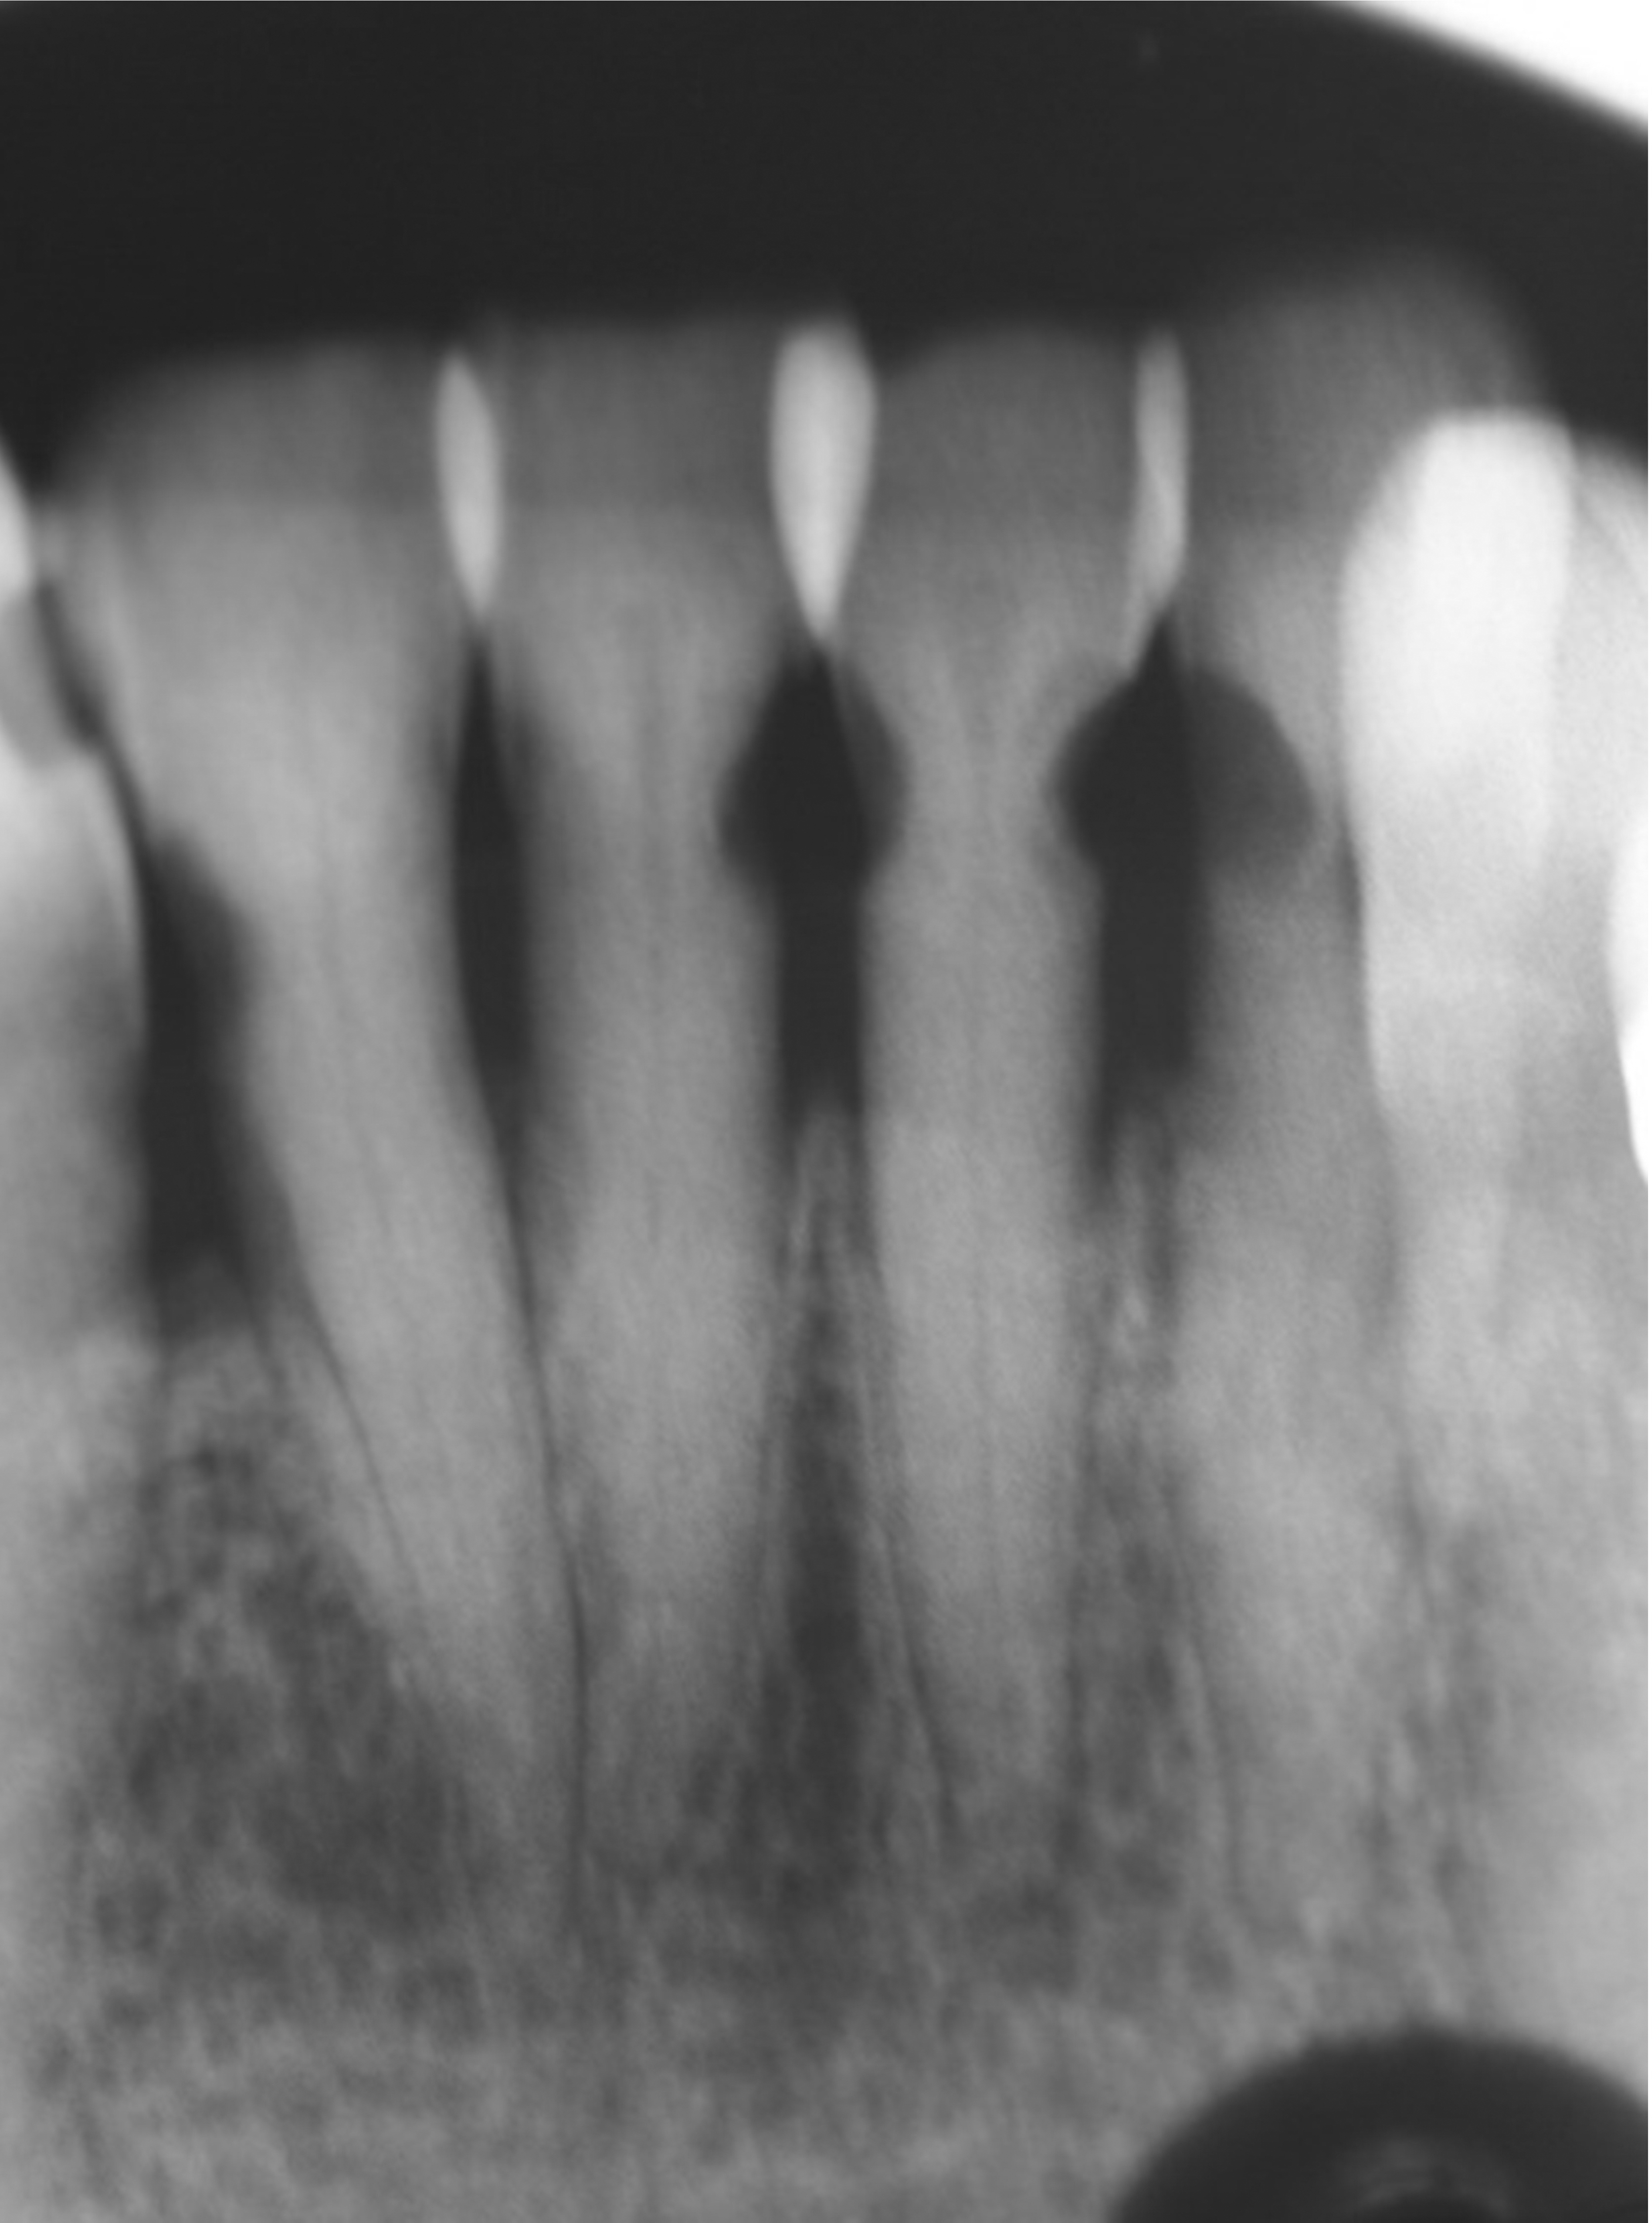

Fig 7. The lower incisors were responsive to electric pulp testing with no radiographic pathology.